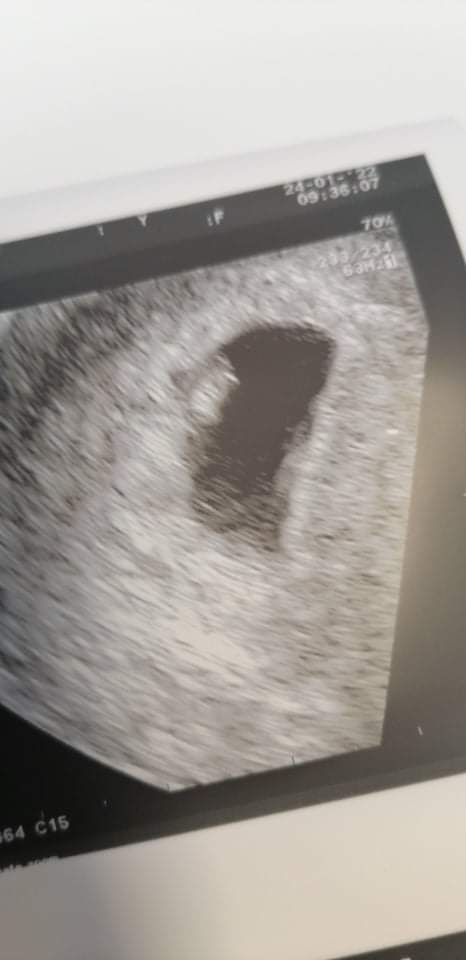

To co ja zacznę.... Przeniosłam wizytę na dzisiaj u innego ginekologa i jestem przeszczesliwa dostałam euthyrox 50 bo mam wysokie anty tpo a tamta gin nie dała mi leków.. Dzisiaj jestem z usg wynika 6+0wedlug apki 6+4.

Moje 3.5mm szczęścia serduszko bije 160/min Jezu jaka ulga... Trzymam kciuki za wszystkie wizyty.....